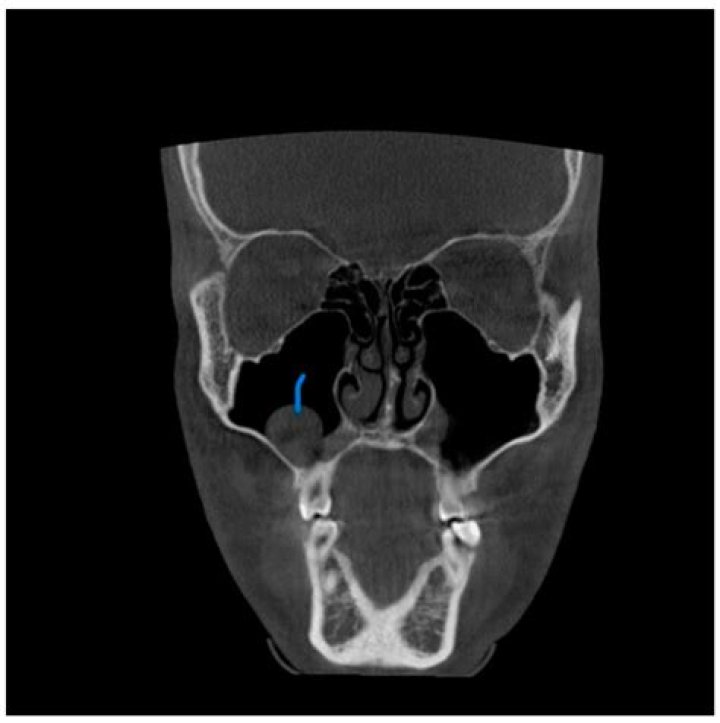

Score: 4.4/5 (17 votes) Maxillary sinus retention cysts (MSRCs) are very common and most of them are asymptomatic and incidentally found on radiographs. ...